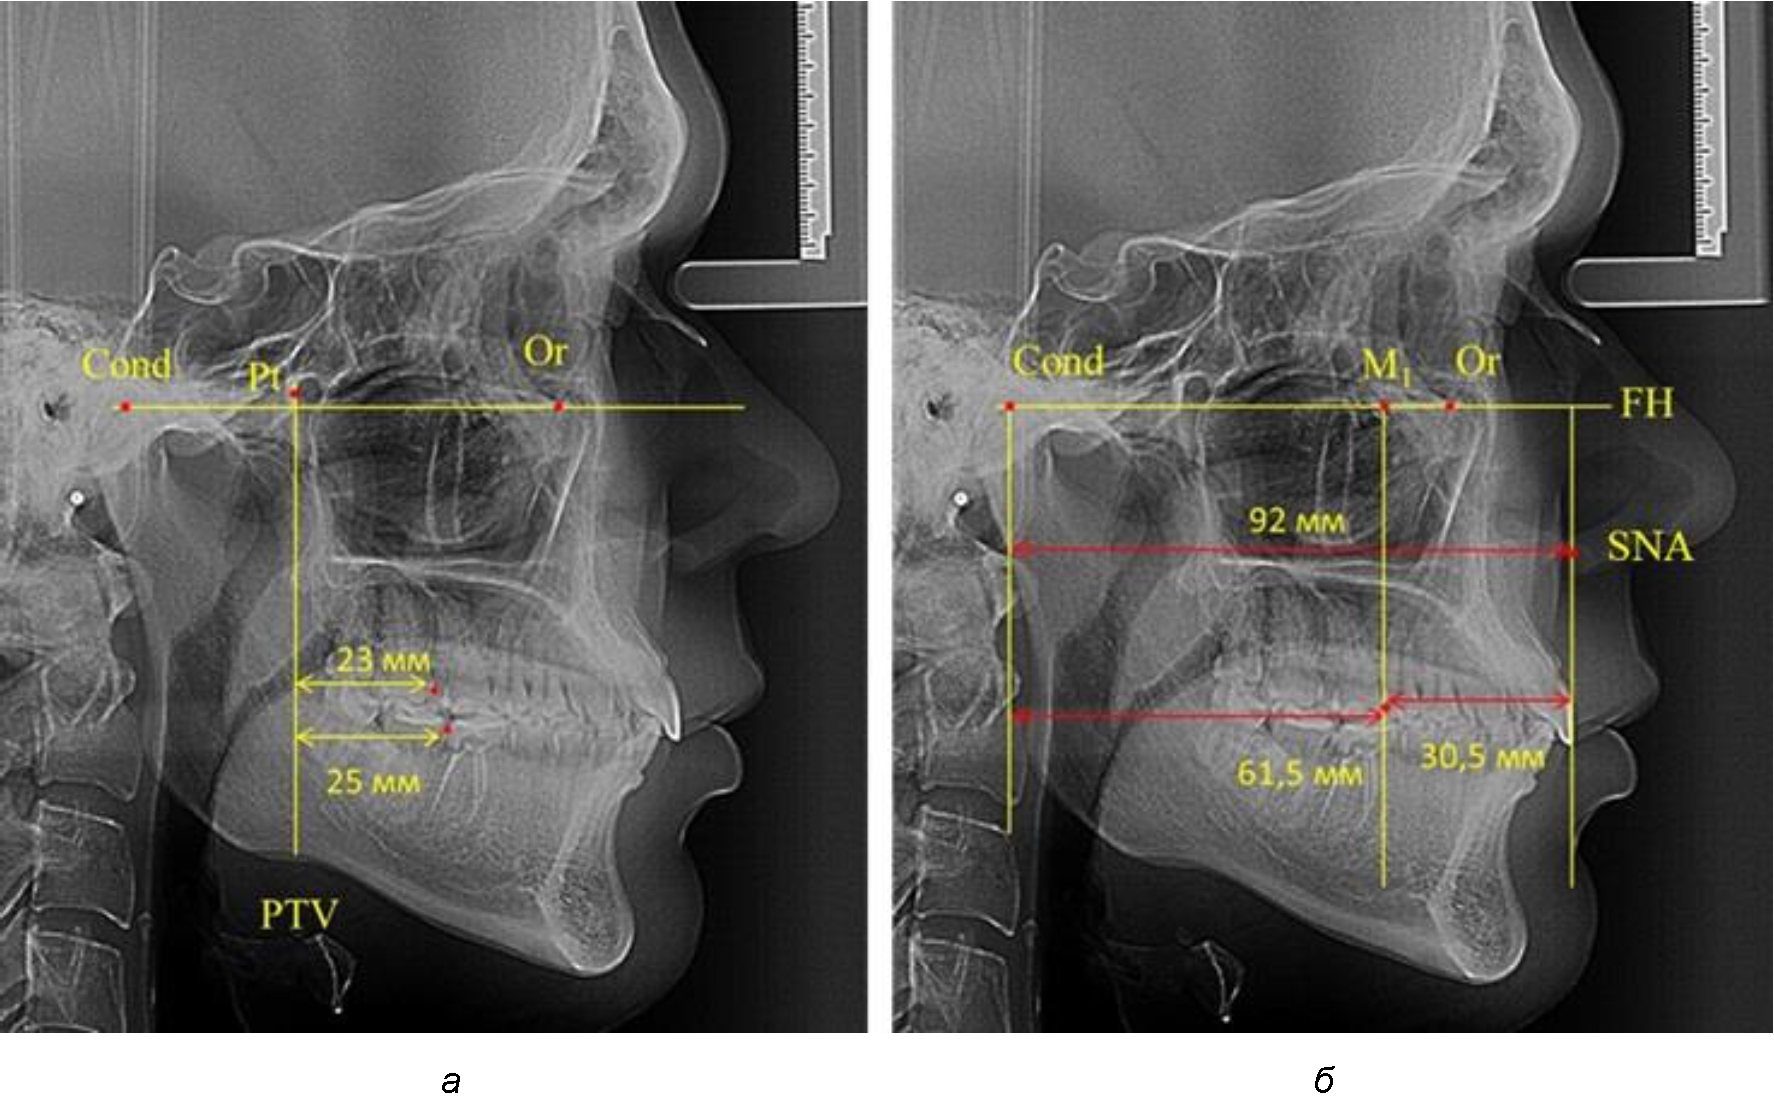

Рис. 1. Метод определения положения первых верхних моляров по Ralph E. McDonald (а) и по предложенному методу (б)

Анализ проведенного исследования рентгенограмм показал существенную вариабельность практически всех линейных показателей. У молодых людей с физиологическим прикусом постоянных зубов расстояние от крыловидной вертикальной плоскости PTV до дистальной поверхности верхнего первого постоянного моляра в целом по группе составляло (18,37 ± 3,62) мм. Обращает на себя внимание большая ошибка репрезентативности из-за разницы между максимальными и минимальными значениями.

Среди анализируемых рентгенограмм минимальное значение расстояния по методу R. E. McDonald было 12 мм, а максимальное достигало 25 мм, что, по нашему мнению, обусловлено вариабельностью сагиттального размера гнатического отдела лица.

Среднее расстояние между суставной (кондилярной) и спинальной вертикалями в анализируемой группе составило (89,12 ± 2,8) мм. При этом сагиттальный размер в среднем составлял (58,74 ± 1,57) мм, а передний размер был (30,41 ± 1,02) мм. Несмотря на вариабельность размеров и большую ошибку репрезентативности, относительно стабильным показателем было отношение сагиттального размера гнатического комплекса к заднему отделу, которое составляло в среднем 1,5 ± 0,06.

Таким образом, для прогнозирования оптимального положения первых постоянных моляров наиболее целесообразным методом явилось использование относительного показателя, что подтверждено при анализе рентгенограмм с минимальными и максимальными значениями по методу R. E. McDonald.

Так, при расстоянии от крыловидной вертикальной плоскости PTV до дистальной поверхности верхнего первого постоянного моляра в 13 мм сагиттальный размер гнатического отдела был 82 мм. При этом отношение кондилярно-спинального расстояния к кондилярно-молярному размеру (54,5) было близким к коэффициенту 1,5, что представлено на рис. 2.

В то же время при увеличенном расстоянии от крыловидной вертикальной плоскости PTV до дистальной поверхности верхнего первого постоянного моляра, равное 23 мм, сагиттальный размер гнатического отдела составил 92 мм. При этом отношение кондилярно-спинального расстояния к кондилярно-молярному размеру (30,5), так же, как и при малых размерах, было близким к коэффициенту 1,5, что представлено на рис. 3.

Таким образом, наблюдалась эффективность использования относительных показателей при определении положения первых постоянных моляров. При этом наиболее целесообразно и с методологической точки зрения верным, было использование медиальной поверхности первого постоянного моляра. Построенная таким образом молярная линия отграничивала отдел зубной дуги с замещающими зубами от дистального отдела с добавочными зубами постоянного прикуса, в частности, постоянных моляров.

Рис. 2. Особенности положения первых моляров по R. E. McDonald (а) и по предложенному методу (б) при уменьшенном молярно-крыловидном расстоянии

Рис. 3. Особенности положения первых моляров по R. E. McDonald (а) и по предложенному методу (б) при увеличенном молярно-крыловидном расстоянии